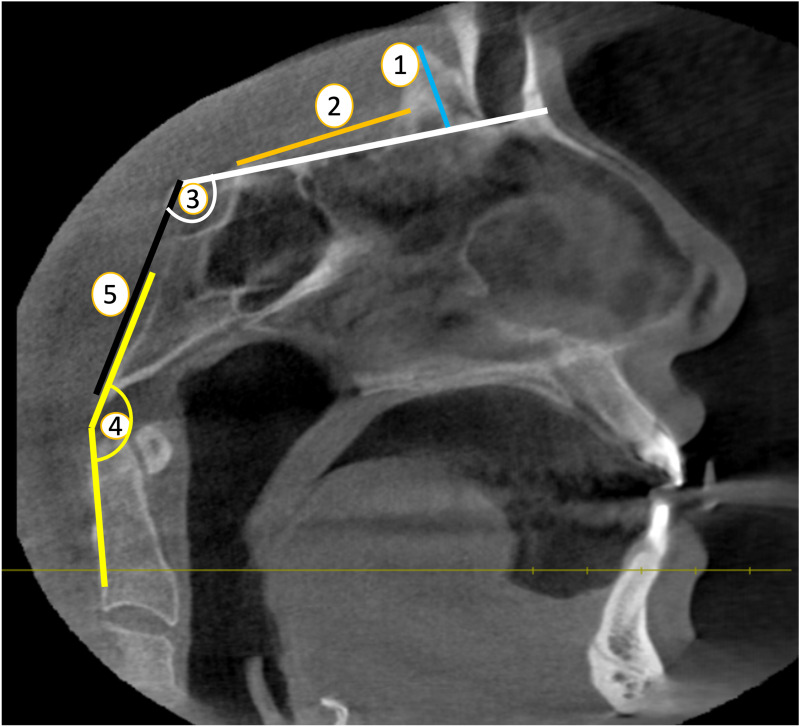

On a midline sagittal image, the height of the crista galli (HCG) and the distance between the crista galli and anterior tuberculum sellae (CG-ATS) were measured.

HCG was defined as the maximum distance between the apex and base of the crista galli. (ref. Marques et al., 2012) (Fig. 2, point 1).

The CG-ATS was determined by measuring the distance from the back edge of the crista galli to the area of the anterior tuberculum sellae, extending to the end of the planum sphenoidale (ref. Batista et al., 2015) (Fig. 2, point 2).

In order to find the basal angle (BA), two lines were drawn on the sagittal plane, one from the nasion to the dorsum sellae and the other from the dorsum sellae to the basion (ref. Botelho & Ferreira, 2013) (Fig. 2, point 3).

The clivus-canal angle (CCA) is determined by measuring the angle formed by a line extending from the lower one-third of the clivus and a line extending from the lower back part of the C-2 vertebral body to the upper back portion of the dens on the sagittal plane. (ref. Botelho & Ferreira, 2013) (Fig. 2, point 4).

Clivus length (CL) was determined by calculating the distance between the dorsum sellae and the bason on a midline sagittal plane (ref. Dufton et al., 2011) (Fig. 2, point 5).